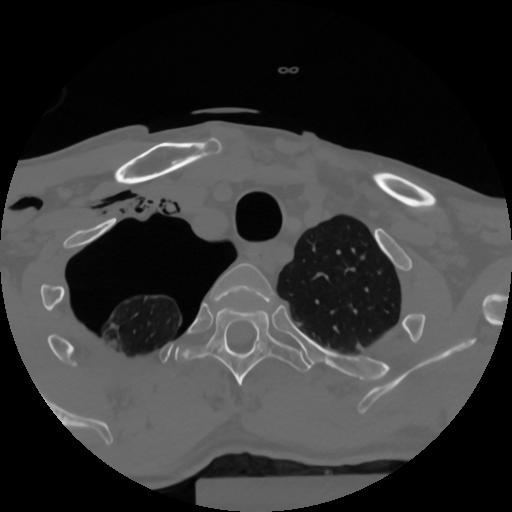

12 P.BLANDAS,,Vol,0.5,P.BLANDAS,,